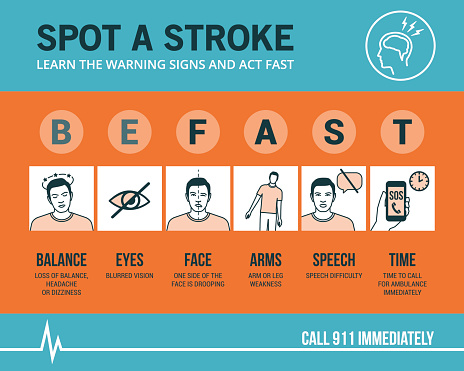

World heart day: Enlarged heart, diabetes and heart disease, fluid around the heart, massive heart attack

September 29th is World Heart Day, which is held and organized by the world heart foundation. The purpose of this occasion is to inform people about cardiovascular diseases, which cause many cases of preventable death in the world. To better facilitate this purpose, we have compiled a list of articles to help get you started ...click here to read more